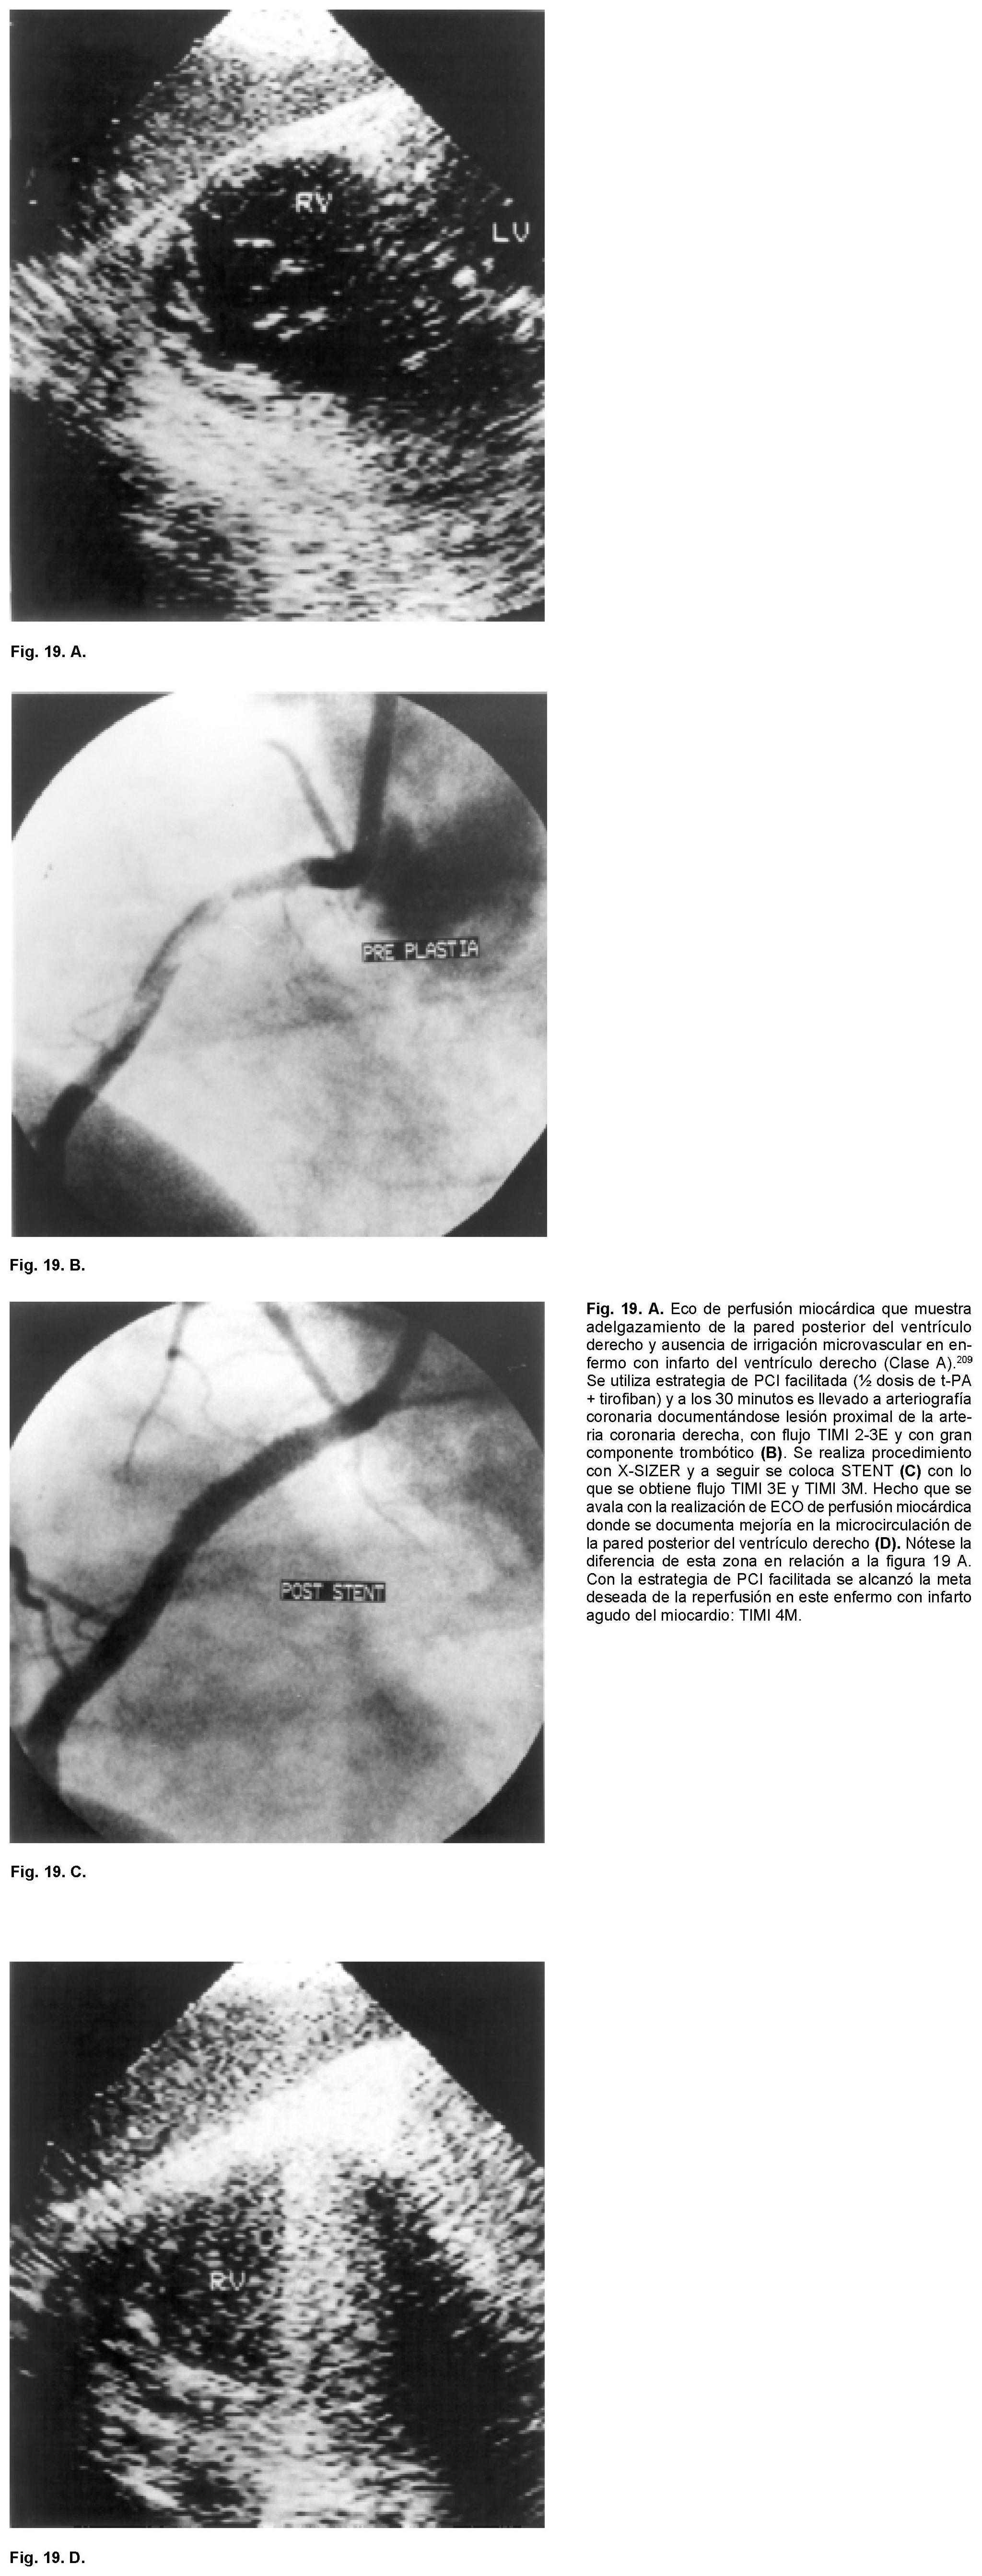

Sabemos que hace 70 años la mortalidad del IAM era cercana al 40%, misma que se logró reducir al 25% a principios de 1951 con la simple maniobra de la movilización temprana y al 20% con la creación de las Unidades Coronarias en 1973. Es en 1987, con la introducción de la terapia fibrinolítica que se establece un nuevo descenso para considerarse cercana al 8%. Ya perfeccionada la terapia de reperfusión y con la introducción de los PCI (angioplastía con balón y mallas endovasculares coronarias) es que tenemos un resultado que oscila del 4 al 6% de mortalidad del IAM (Fig. 10). Es por eso que hoy día se acepta que esta modalidad terapéutica es la que ha sido capaz de brindar el más importante descenso de la mortalidad en el rubro del IAM transmural. Entre los factores más importantes de los que depende alcanzar esta reducción está el factor tiempo relacionado al momento en el que se de el tratamiento o ventana terapéutica en la que se aplique la terapia de reperfusión. La magnitud de miocardio salvado determinada experimentalmente para el ventrículo izquierdo es cercano al 70% si la reperfusión se realiza en la primera hora a partir de haberse ocluido la arteria epicárdica. Disminuye al 40% a la tercera y al 20% a la sexta, para ser menor del 5% a las 24 horas. Para el ventrículo derecho Lester y colaboradores124 han encontrado que el área de infarto a la hora de reperfusión es de tan sólo un cinco por ciento, a las cuatro horas es de un 10% y a las ocho es del 20%. Por lo tanto, el acortar el tiempo de la reperfusión para cualquiera de ambas cámaras ventriculares sería igual a menor daño miocárdico o mayor magnitud de miocardio salvado. Esta es una de las razones por la que después de seis horas el beneficio de la reperfusión de la arteria epicárdica decae significativamente para considerarla casi nula después de doce horas. Lo que se aplica tanto para el tratamiento fibrinolítico como para los PCI. Si en la ARI no se obtiene permeabilidad inmediata la mortalidad es del 17.5%, lo que equivale a remontarnos a la consignada en los años de 1970. Si la ARI está permeable a los 90 minutos pero se le encuentra ocluida al séptimo día, la mortalidad es del 12% lo cual nos ubica en la mortalidad documentada a principios de 1980. Si la ARI está permeable a los 90 minutos y al séptimo día la mortalidad es del 4.7%. Por otro lado, la importancia de la calidad del flujo epicárdico post reperfusión resulta extraordinariamente relevante. Las primeras observaciones en este sentido con la terapia de reperfusión lítica nos demostraron que cuando el flujo epicárdico es TIMI: 0 -1 la mortalidad del IAM es del 8.9%, al ser grado TIMI: 2 la mortalidad es del 7.4% y con TIMI: 3 epicárdico es del 4.4% (Figs. 8 y 11 A - 11 B). Pero por fortuna hemos avanzado en el conocimiento en este sentido y con la valiosa información del estudio GUSTO II b (The Global Use of Strategies to open Occluded Coronary Arteries in Acute Coronary Syndromes) sabemos que con ACTP de obtenerse flujo TIMI 0-1-2 la mortalidad es del 18 - 20%, cifras que resultan casi del doble de las documentadas con trombólisis para los mismos flujos, hecho interesante que nunca se ha explicado claramente.125 En cambio de obtenerse flujo TIMI 3E la mortalidad a treinta días es de tan sólo 1.6%, observándose menor tamaño del área infartada y mayor índice de miocardio salvado. Lo que establece sólo una diferencia del 2.8% entre las dos estrategias de reperfusión cuando se alcanzan flujos TIMI 3E (Fig. 8). Para llegar a estas conclusiones, frente a los enfermos es menester tomar en consideración los datos relevantes proporcionados por Gibson y colaboradores en relación al análisis angiográfico de la perfusión miocárdica.126 Mismo que se ha valorado por dos métodos pero que al final sólo traducen que existe perfusión a nivel de la microvasculatura. Empero hay que recordar que existen varios factores de los que también depende el flujo TIMI epicárdico como son los de orden: hemodinámico, la anatomía local de la arteria, la propia técnica del procedimiento, el trombo intracoronario y aspectos derivados del intervencionismo: la estenosis residual, la disección involuntaria de la arteria coronaria y menos relevantes parecen la aplicación de las mallas endocoronarias (Fig. 12).126 Excluidas estas causales, quedarían las dos más importantes a considerar: la obstrucción microvascular y las que son producto del fenómeno de no flujo en la microcirculación. El flujo TIMI en la microcirculación se expresa o se visualiza en la angiografía coronaria como áreas de condensación de aspecto esmerilado muy finas del material de contraste a nivel del miocardio. Esto es lo que los autores anglosajones designan en su lengua como "blush" y que correspondería a "TIMI miocárdico 4".127-130 Si bien las anomalías de la microcirculación se han demostrado de manera fehaciente por los diferentes métodos citados con antelación, si se cuestiona si lo que documentamos es también producto de edema miocárdico y/o del daño por reperfusión. Sin embargo este patrón de alteración microcirculatoria ocurre tempranamente (en las primeras horas o días), lo que hace menos probable que sea por daño por reperfusión. Es más, se le ha documentado en sujetos que van a PCI (rotaablación coronaria) y tras la práctica de ellos aparecen cambios miocárdicos en los estudios de perfusión nuclear, lo que sugiere embolización a la microcirculación (Fig. 13). 121,122 Con la utilización de catéteres con redes o sistemas de aspiración se han recuperado fragmentos del material que hubiesen sido embolizados. Por lo tanto, en la clínica se puede decir que este mecanismo se sugiere como la causa primordial, al menos en etapas tempranas, de las anomalías documentadas en la microcirculación. Mas es innegable que en el caso de IAM transmural reperfundido deberán estar presentes los dos mecanismos, el inicial ligado a la microembolización y el tardío aunado a los fenómenos de la injuria post reperfusión (Fig. 5). Lo importante es que la obstrucción microvascular está vinculada a mal pronóstico aún de obtenerse la permeabilidad deseada de la arteria epicárdica. Wu y colaboradores131 han demostrado que a 25 meses el 90% de los enfermos sin OMV están libres de muerte-reinfarto e insuficiencia cardiaca. De existir OMV tan sólo el 55% lo estarán. Es más, con estudios de resonancia magnética nuclear se ha podido catalogar la magnitud de los defectos en áreas grandes, moderadas y pequeñas de OMV con diferencias estadísticas en morbimortalidad de cada una de estos grupos y directamente proporcionales a la magnitud del defecto documentado en la resonancia magnética nuclear. Uno de los primeros estudios en llamar la atención en la posibilidad de microembolización ligada a PCI fue el CAVEAT (Coronary Angioplasty Versus Excisional Atherectomy) donde la incidencia de IAM fue superior a la esperada. Se encontró una frecuencia de IAM del 3% para ACPT y del 6% para aterectomía rotacional. En este estudio prospectivo la elevación de la CK-MB a cifras tres veces por arriba del valor basal fue de 8% para la ACTP y del 19% para la aterectomía.121 En el estudio CAVEAT II sobre intervenciones en libramientos de venas safenas la incidencia de IAM fue considerablemente mayor 15 y 24% respectivamente.122 En nuestro medio Vallejo E y colaboradores132 revisaron 204 angioplastías electivas y 62 primarias. El fenómeno de no flujo predominó en hombres, con edad promedio de 56 años y fue la diabetes mellitus un factor de mayor riesgo para observarlo. La incidencia global del problema fue del 5.2%, 16.1% para la angioplastía primaria y del 1.9% en los procedimientos intervencionistas electivos. Por lo tanto, los autores no la consideran como una complicación rara o infrecuente particularmente en el escenario del IAM. Este importante hallazgo de todos los estudios previamente mencionados dio origen a ciertos debates, si los procedimientos intervencionistas utilizados creaban fuga enzimática, eran capaces de dar seudoinfartos o microinfartos.66 En el seguimiento a largo plazo se demostró un exceso de mortalidad para la aterectomía y aquellos que fallecieron presentaron durante el procedimiento cambios dinámicos del segmento ST muy sugestivos de IAM no transmural o subendocárdico. Varios estudios posteriores han demostrado que a mayor elevación de la CK-MB post PCI hay mayor probabilidad de muerte.121,122 Así cuando la elevación de CK-MB es de cinco veces el valor basal, la mortalidad al año es de 6 -7%, de ser 10 veces el incremento de CK-MB es del 13%. La posible causa de este hallazgo es la microembolización coronaria ya que otras eventualidades son menos frecuentes o resultan menos probables como factores causales tales como el tiempo de isquemia ocasionado por el balón que es habitualmente demasiado corto para ocasionar necrosis per se. Las oclusiones abruptas de ramas coronarias epicárdicas hoy día son poco frecuentes (< 3%) y la oclusión sú bita coronaria transitoria se le ve en menos del 1%.135 La incidencia por lo tanto de grados diversos de micromionecrosis, consecuencia de la embolización coronaria, al menos significativa no parece despreciable. Valorada utilizando biomarcadores como la Troponina T o I parece cercana al 30 - 40%. Si bien la identificación alta de troponinas post intervención parece importante, también lo es cuando se documentan elevaciones de la misma antes de realizar los PCI.136,137 Así Hamm y cols138 han demostrado que hay una respuesta diferente al tratamiento con bloqueadores de los receptores plaquetarios. Aquellos con Troponina T positiva al ingreso responden favorablemente al inhibidor del receptor plaquetario por el bloqueo del mecanismo citado a nivel de la microcirculación, además de reducir la frecuencia del trombo en la arteria epicárdica sometida a ACTP o a la colocación del stent.

Varios métodos se han utilizado para la valoración cuantitativa de la perfusión microvascular, lo que nos da una información muy valiosa de lo que está aconteciendo en el tejido miocárdico postpermeabilización de la ARI (Figs. 11 A y B). Estos procedimientos diagnósticos serán mencionados a continuación.